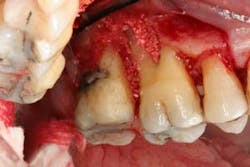

Figures 6a and 6b: Osseous surgery in the upper left quadrant with debridement of root surfaces, extraction of No. 15, and then regeneration.

Briefly, during osseous surgery, the upper right molars were treated with a combination of autograft and platelet-derived growth factor/Beta-tricalcium phosphate along with a porcine collagen graft (figures 5a and 5b). The upper left osseous surgery consisted of the same treatment (figures 6a and 6b), but also included the extraction of a hopeless tooth No. 15. Once again, the anterior osseous surgery consisted of the same regenerative materials as the former surgeries but with the addition of a porcine soft-tissue graft (figures 7a, 7b, and 7c). After the initial healing phase, the patient was placed on a strict home-care regimen and was seen every eight to 12 weeks for hygiene recare. The patient maintained excellent hygiene throughout the five-year follow-up period.